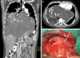

Large unilateral intrathoracic mass